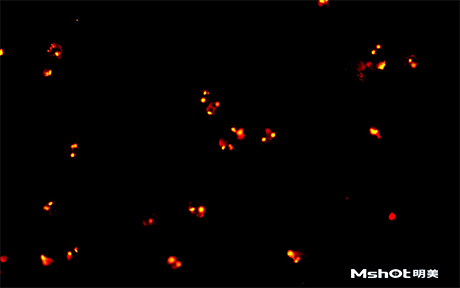

北京某试剂单位已有一台奥林巴斯生物显微镜BX61,希望能进行CTC检测,在电脑中成像拍摄保存图片,刚好我们在北京有办事处,工程师了解到具体需求分析后提供一款明美数字摄像头MS23,搭配奥林巴斯BX61生物显微镜在40X观察下,效果如图: